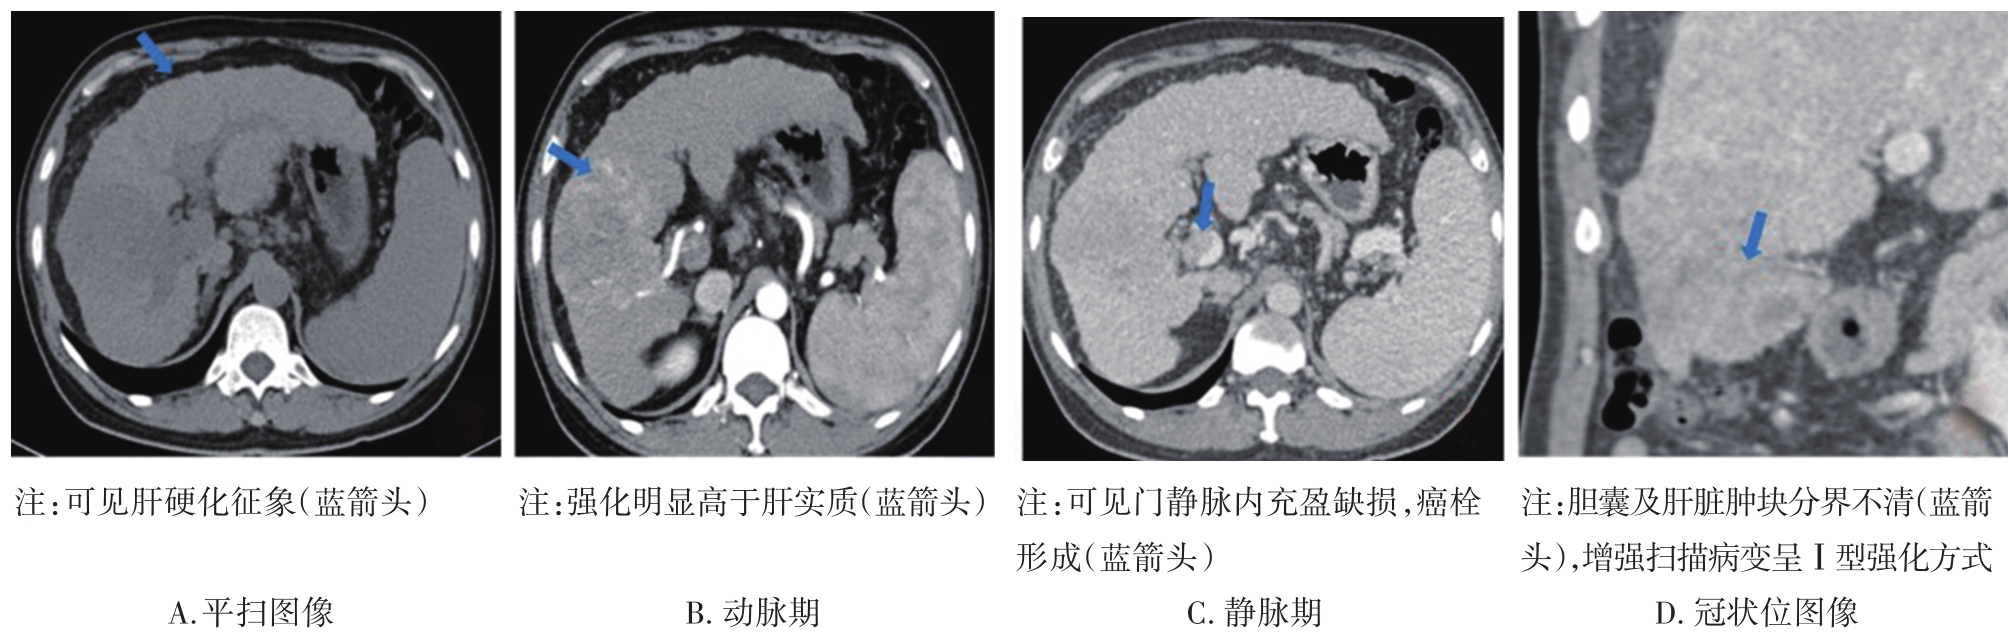

• 探讨增强CT在鉴别胆囊癌侵犯肝脏与肝癌累及胆囊病变中的应用价值

摘要:目的 探讨增强电子计算机断层扫描(computer tomography,CT)在胆囊癌侵犯肝脏与肝癌累及胆囊病变中的鉴别诊断价值。方法 收集2012年2月到2022年2月重庆医科大学附属第一医院115例患者临床及影像学资料,其中胆囊癌侵犯肝脏病例69例,肝癌累及胆囊病例46例,记录性别、年龄、肿瘤大小、肿瘤边界、胆囊形态、肝硬化、胆管扩张、肿瘤内或胆管系统内高密度影、门静脉癌栓、强化方式、强化程度、淋巴结肿大及远处转移共13个观察指标,并进行统计学分析。结果 性别(P=0.007)、年龄(P=0.002)、肿瘤大小(P=0.003)、肝硬化(P<0.001)、肿瘤内或胆管系统内高密度影(P=0.013)、门静脉癌栓(P<0.001)、强化方式(P<0.001)及淋巴结肿大(P=0.034)有统计学差异。通过回归分析筛选出年龄(敏感度为0.812,特异度为0.457)、肿瘤大小(敏感度为0.630,特异度为0.696)、门静脉癌栓(敏感度为0.326,特异度为0.957)、淋巴结肿大(敏感度为0.681,特异度为0.522)为显著分类指标,联合4个观察指标的参数绘制受试者工作特征(receiver operating characteristic,ROC)曲线,曲线下面积(area under the curve,AUC)为0.770,敏感度为0.674,特异度为0.826。结论 增强CT在鉴别胆囊癌侵犯肝脏与肝癌累及胆囊病变时,性别、年龄、肿瘤大小、肝硬化、肿瘤内或胆管系统内高密度影、门静脉癌栓、强化方式及淋巴结肿大有鉴别价值,同时结合年龄、肿瘤大小、门静脉癌栓及淋巴结肿大有助于提高鉴别诊断能力。